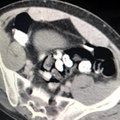

Zanlının bağırsak filmi

-Filmde bağırsaklarında yabancı cismin belli olması

Van-Adana uçağı havalimanına iniş yapınca zanlı polis tarafından gözaltına alındı. Zanlı emniyete getirilerek sorguya alındı. Polis yaptığı bagaj ve üst aramasında uyuşturucuya rastlamadı. Bunun üzerine polis zanlının uyuşturucu yutma yöntemiyle taşıyacağını düşünerek zanlıya bu yöntemi kullanıp kullanmadığını sordu ancak zanlı bunu inkar etti. Polis bunun üzerine savcılıktan alınan izinle zanlıyı Çukurova Üniversitesi Tıp Fakültesi Balcalı Hastanesi Gastroenteroloji Bölümüne götürdü. Burada zanlının bağırsak tomografisi çekildi. Zanlının bağırsaklarında serçe parmağı büyüklüğünde yabancı cisimler olduğu tespit edildi. Buna rağmen zanlı uyuşturucu olmadığını ileri sürmeye devam etti. Doktorlar zanlıya özel bir ilaç vererek bağırsaklarında yabancı cisimlerin tuvalet yoluyla çıkmasını sağladı. 5 günün sonunda zanlının bağırsaklarından 4 pakette 116 gram metamfetamin, 21 pakette 104 gram eroin, 22 pakette 107 gram afyon sakızı çıktı. Zanlının uyuşturucular çıktıktan sonra ifade değiştirip, "Van'da beni uyutmuşlardı o zaman koymuş olabilirler ne yaptıklarını bilmiyorum benim haberim yok" dediği öğrenildi. Zanlı ifadesi alındıktan sonra adliyeye sevk edildi. Adana'da 21 Aralık 2019 günü de yine havalimanında, Van'dan gelen İran uyruklu Seddigh Raşhıdıtavana (58) isimli şahsın bağırsaklarından 49 pakette 765 gram eroin çıkmıştı. (FKE-